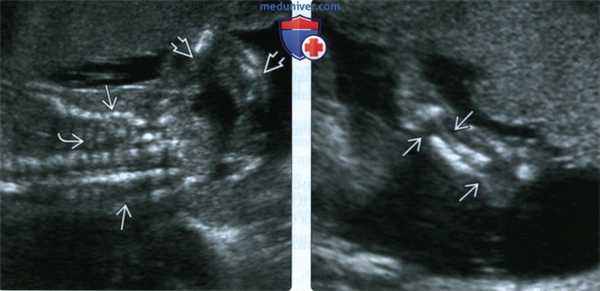

(Слева) УЗИ грудной клетки и верхней конечности плода во II триместре, фронтальная плоскость. Грудная клетка уменьшена, ребра неправильной формы с множеством переломов. Многочисленные переломы костей руки.

(Справа) Тот же случай, визуализация предплечья. Неоднородная оссификация локтевой и лучевой костей. Костные сегменты нередко смещены, за счет чего кость выглядит изогнутой или искривленной. В данном случае диагностирован перинатальнолетальный НО (II тип).